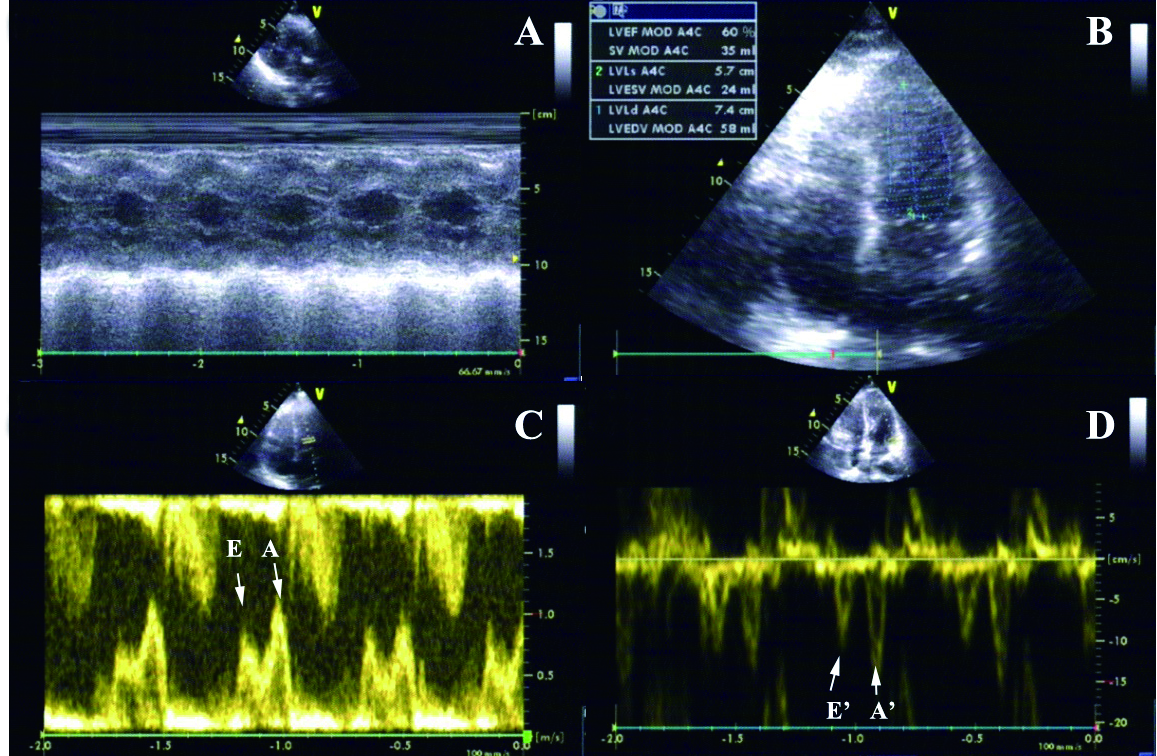

1.2.2 心脏超声选用SIMENS S2000超声诊断仪(SIMENS,德国),凸阵探头,频率为2.546 MHz。患者取左侧卧位,每个参数连续测量3次,取平均值。取胸骨旁左心室长轴切面,测量左心房内径(LAD)、左心室后壁厚度(LVPWd)、室间隔厚度(IVSd)和左心室舒张末内径(LVEDD);在标准心尖四腔心切面上,测量二尖瓣舒张早期血流峰速(E)和舒张晚期血流峰速(A),计算E/A比值;利用改良Simpson单平面法计算LVEF;然后进入组织多普勒成像(tissue Doppler imaging, TDI)模式,将取样容积置于左心室室间隔二尖瓣瓣环水平处,获取DTI图谱,测量二尖瓣环舒张早期速度(E'),并计算E/E'比值(图 1)。

| A:M型超声测量左心参数;B:改良Simpson单平面法计算LVEF;C:E峰即二尖瓣舒张早期充盈速度,A峰即二尖瓣舒张晚期充盈速度;D:E'即二尖瓣环舒张早期速度,A'即二尖瓣环舒张晚期速度 图 1 心脏超声及参数 Figure 1 Parameters of echocardiogram |